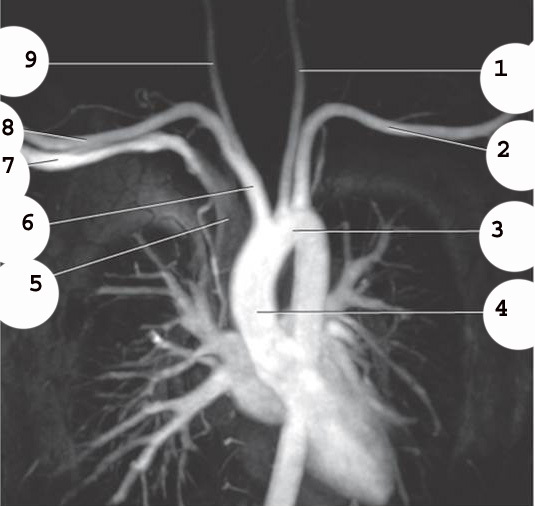

1

L common carotid Artery

2

L subclavian artery

3

AO arch

4

ascending AO

5

SVC

6

Brachiocephalic trunk

7

R subclavian vein

8

R subclavian Artery

9

R common carotid A